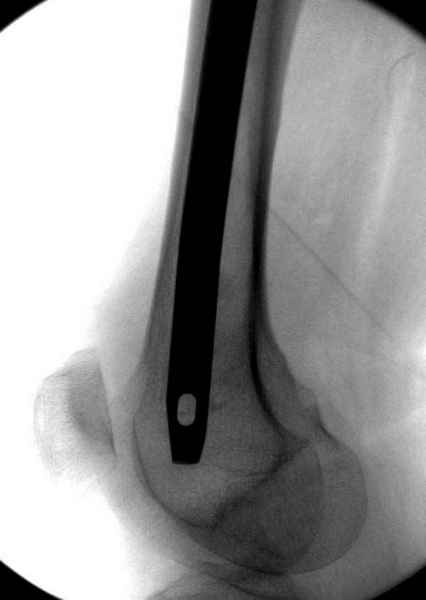

На второй день после выписки упал дома. Снимки приложены. Коллеги рекомендуют удаление шурупа и вытяжение. Что делать?

Наверное речь идет насчет parallel guide из набора. Применяем по возможности всегда, но,

как видно на снимке, не всегда получается

паралельно.

Такие несмещенные переломы обычно для молодых резидентов, и бывают технические неточности, но в этом случае посчитали фиксацию адекватной.

Соблюдая правила, многократными попытками можно

увеличить риск стрессового перелома латерального

кортекса.

Правильно, ситуация изменилась, как говорят у нас теперь "different animal", надо решать проблему подвертельного перелома. При наличии различных вариантов фиксаторов, включая Страйкер Гамма 3, мы выбрали DePuy Antegrade Trachanteric Nail из-за многовариантности проксимальной фиксации и двойного изгиба. Вводится через вертел под 8 градусным углом, и есть достаточный передний диафизарный изгиб, предупреждающий пенетрацию дистального переднего кортекса.